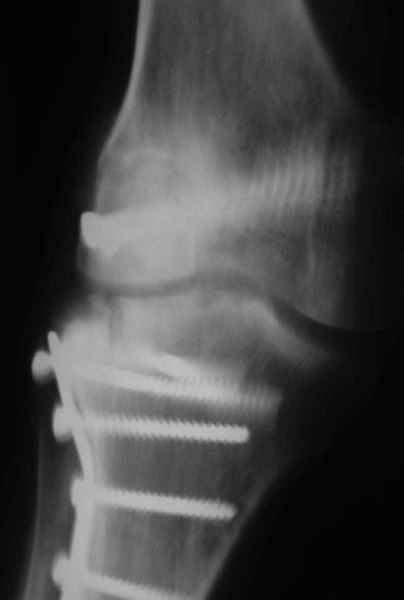

Как вариант решения прогрессирующей вальгусной деформации коленного сустава я бы предложил косую остеотомию дистального отдела бедра с фиксацией пластиной и компрессирующим винтом.

Взгляните на снимки , может быть это вам поможет.

Около 5 лет применяю этот тип дистальной остеотомии бедра для коррекции механической оси Н/К ( более 20 случаев) - достаточно эффективная операция.

Уважаемый Евгений ! Спасибо за ответ, но мне представляется, что в нашем случае основной проблемой является не столько прогрессирующий вальгус конечности, сколько несросшийся перелом мыщелка бедра и дефект мыщелка большеберцой кости - вероятно первичная репозиция выполнялась без пластики.

На своем горьком опыте убедился, что синтезировать мыщелковые импрессионные внутрисуставные переломы б\б кости без костной пластики - дело неблагодарное, рецидивируе деформация, мыщелок всегда *проваливается*. Чистые split type переломы можно ограничиваться и одной только межфрагментарной компрессией.

Может стоит сначала добиться сращения наружного мыщелка бедра( костная пластика) и коррекции оси?

Мне представляется, что прогрессирующий вальгус и обусловлен несросшимся переломом мыщелка бедра (томограммы -зона межфрагментарного склерозирования), а циклические нагрузки на сустав во время ходьбы усугубляют ситуацию. Как вы думаете, в этой ситуации насколько вероятен риск развития аваскулярного некроза мыщелка бедра?

Относительно "рубцовой подушки" я имел в виду остатки мениска ( частично вколоченного в дефект мыщелка и фрагменты хряща), все таки на рентгенограммах суставная щель в этом отделе чем то заполнена. Что касается некроза мыщелка бедра, то мне кажется он уже наступил - томограмма ноябрь5.

С учетом всего сказанного - наличия прогессирующего вальгуса конечности, довольно приличного объема движений, имеющегося, вероятно, некроза мыщелка бедра, наиболее рациональным представляется удалить пластину с б\б кости, произвести остеотомию б\б кости с коррекцией вальгуса, разгрузив тем самым наружный отдел сустава, и синтезировать фрагменты голени накостным фиксатором. Максимально тано начать восстановление движений в суставе. Скорее всего рано или поздно речь о протезировании всеже возникнет, но мы хотя бы будем иметь приличную ось конечности.

Тут ситуация совсем другая. Деформация не около-, а самая что ни на есть внутрисуставная. Покорректировать внешний вид конечности путем остеотомии дистального отдела бедра и high tibia (плюс или минус клин, одномоментно-постепенно, аппарат-пластина-стержень - дело третье) не сильно сложно, но это не решение проблемы. У больной, по

сути отсуствует латеральный отдел коленного сустава, что требует костно-пластических вмешательств непосредственно на артикулирующих

поверхностях.

Может быть, целесообразней сразу протез, чем тот же протез, но после сложных, но сомнительно результативных операций типа замещения алломыщелком, моделирующих резекций и т.п.? Ну и в любом случае движения лучше бы разработать получше до любой операции.